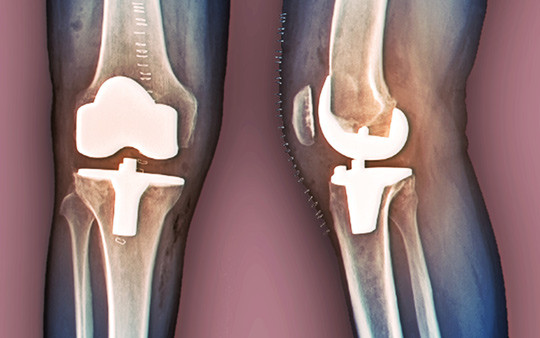

Operativ behandling med total kneprotese kan gi bedre resultater enn konservativ behandling hos pasienter med moderat til alvorlig kneleddsartrose, men kan også føre til komplikasjoner.

Illustrasjonsfoto: Science Photo Library